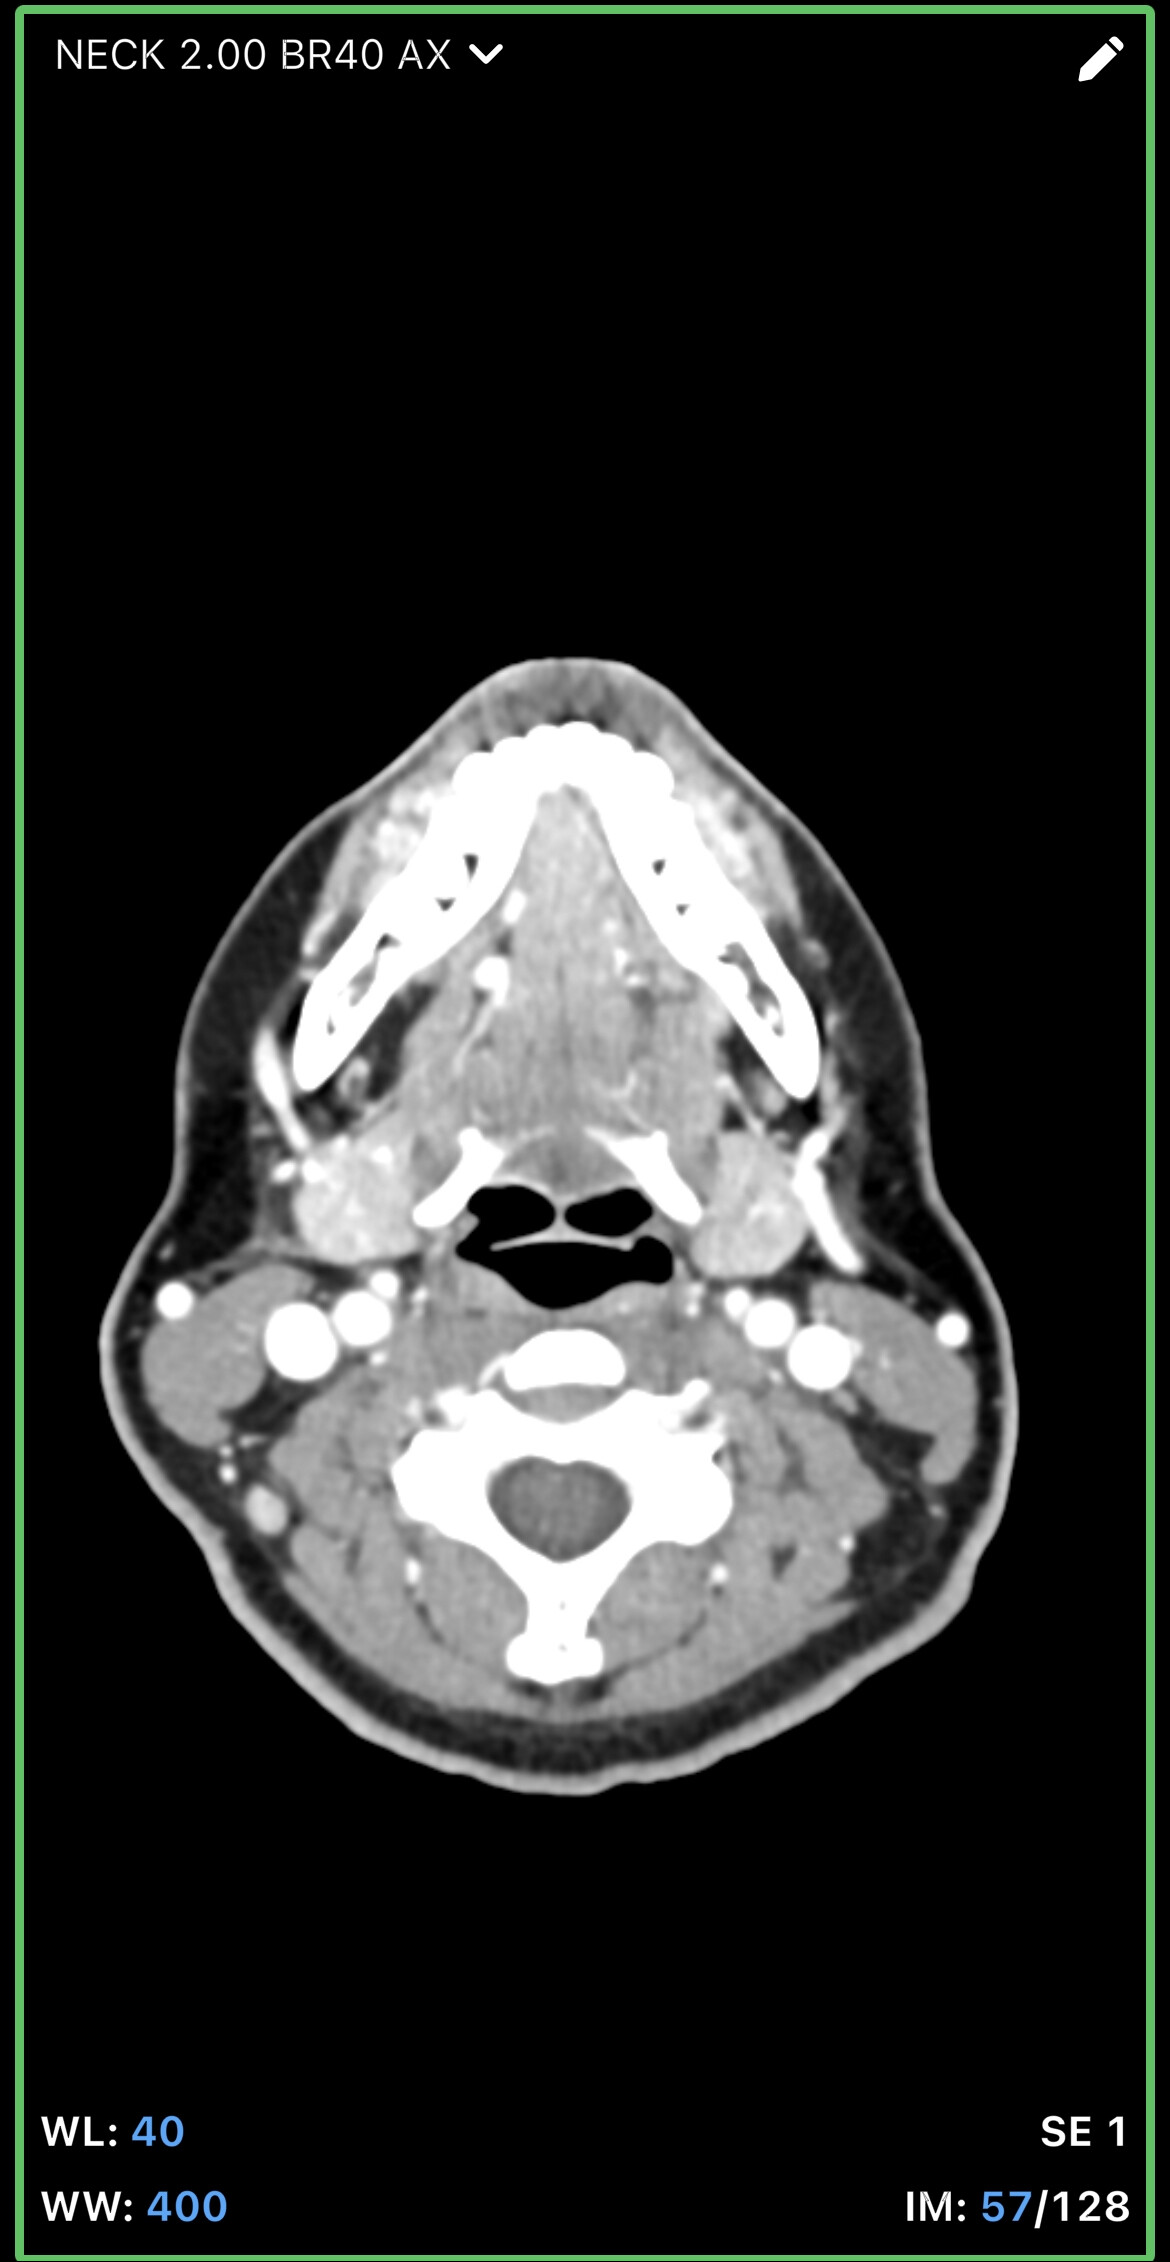

In your first & last pictures, you can see how close to your spine the greater horns of your hyoid are. Your whole hyoid looks like it’s been pushed back further in your neck than it should be possibly producing Hyoid Bone Syndrome (HBS).

@leo this is the closest one. Can you go back to your axial view and go to the very last slice that you can see the tips? I think you might be one or two frames off. I attached my imaging to help. Our hyoids might be at slightly different angles so it might not be a perfect comparison, but I think you can go up a slice or two to see the tips better. Basically follow the bone until it disappears then go back one frame to capture it.

@leo - The new symptoms you’ve just mentioned i.e. dizziness, headaches, brain fog, weird throbbing in my neck and head are all those we see associated with internal jugular vein compression. From what I can see in the images you posted, it looks like you may have that going on, but I’ll let @TML give you more information.